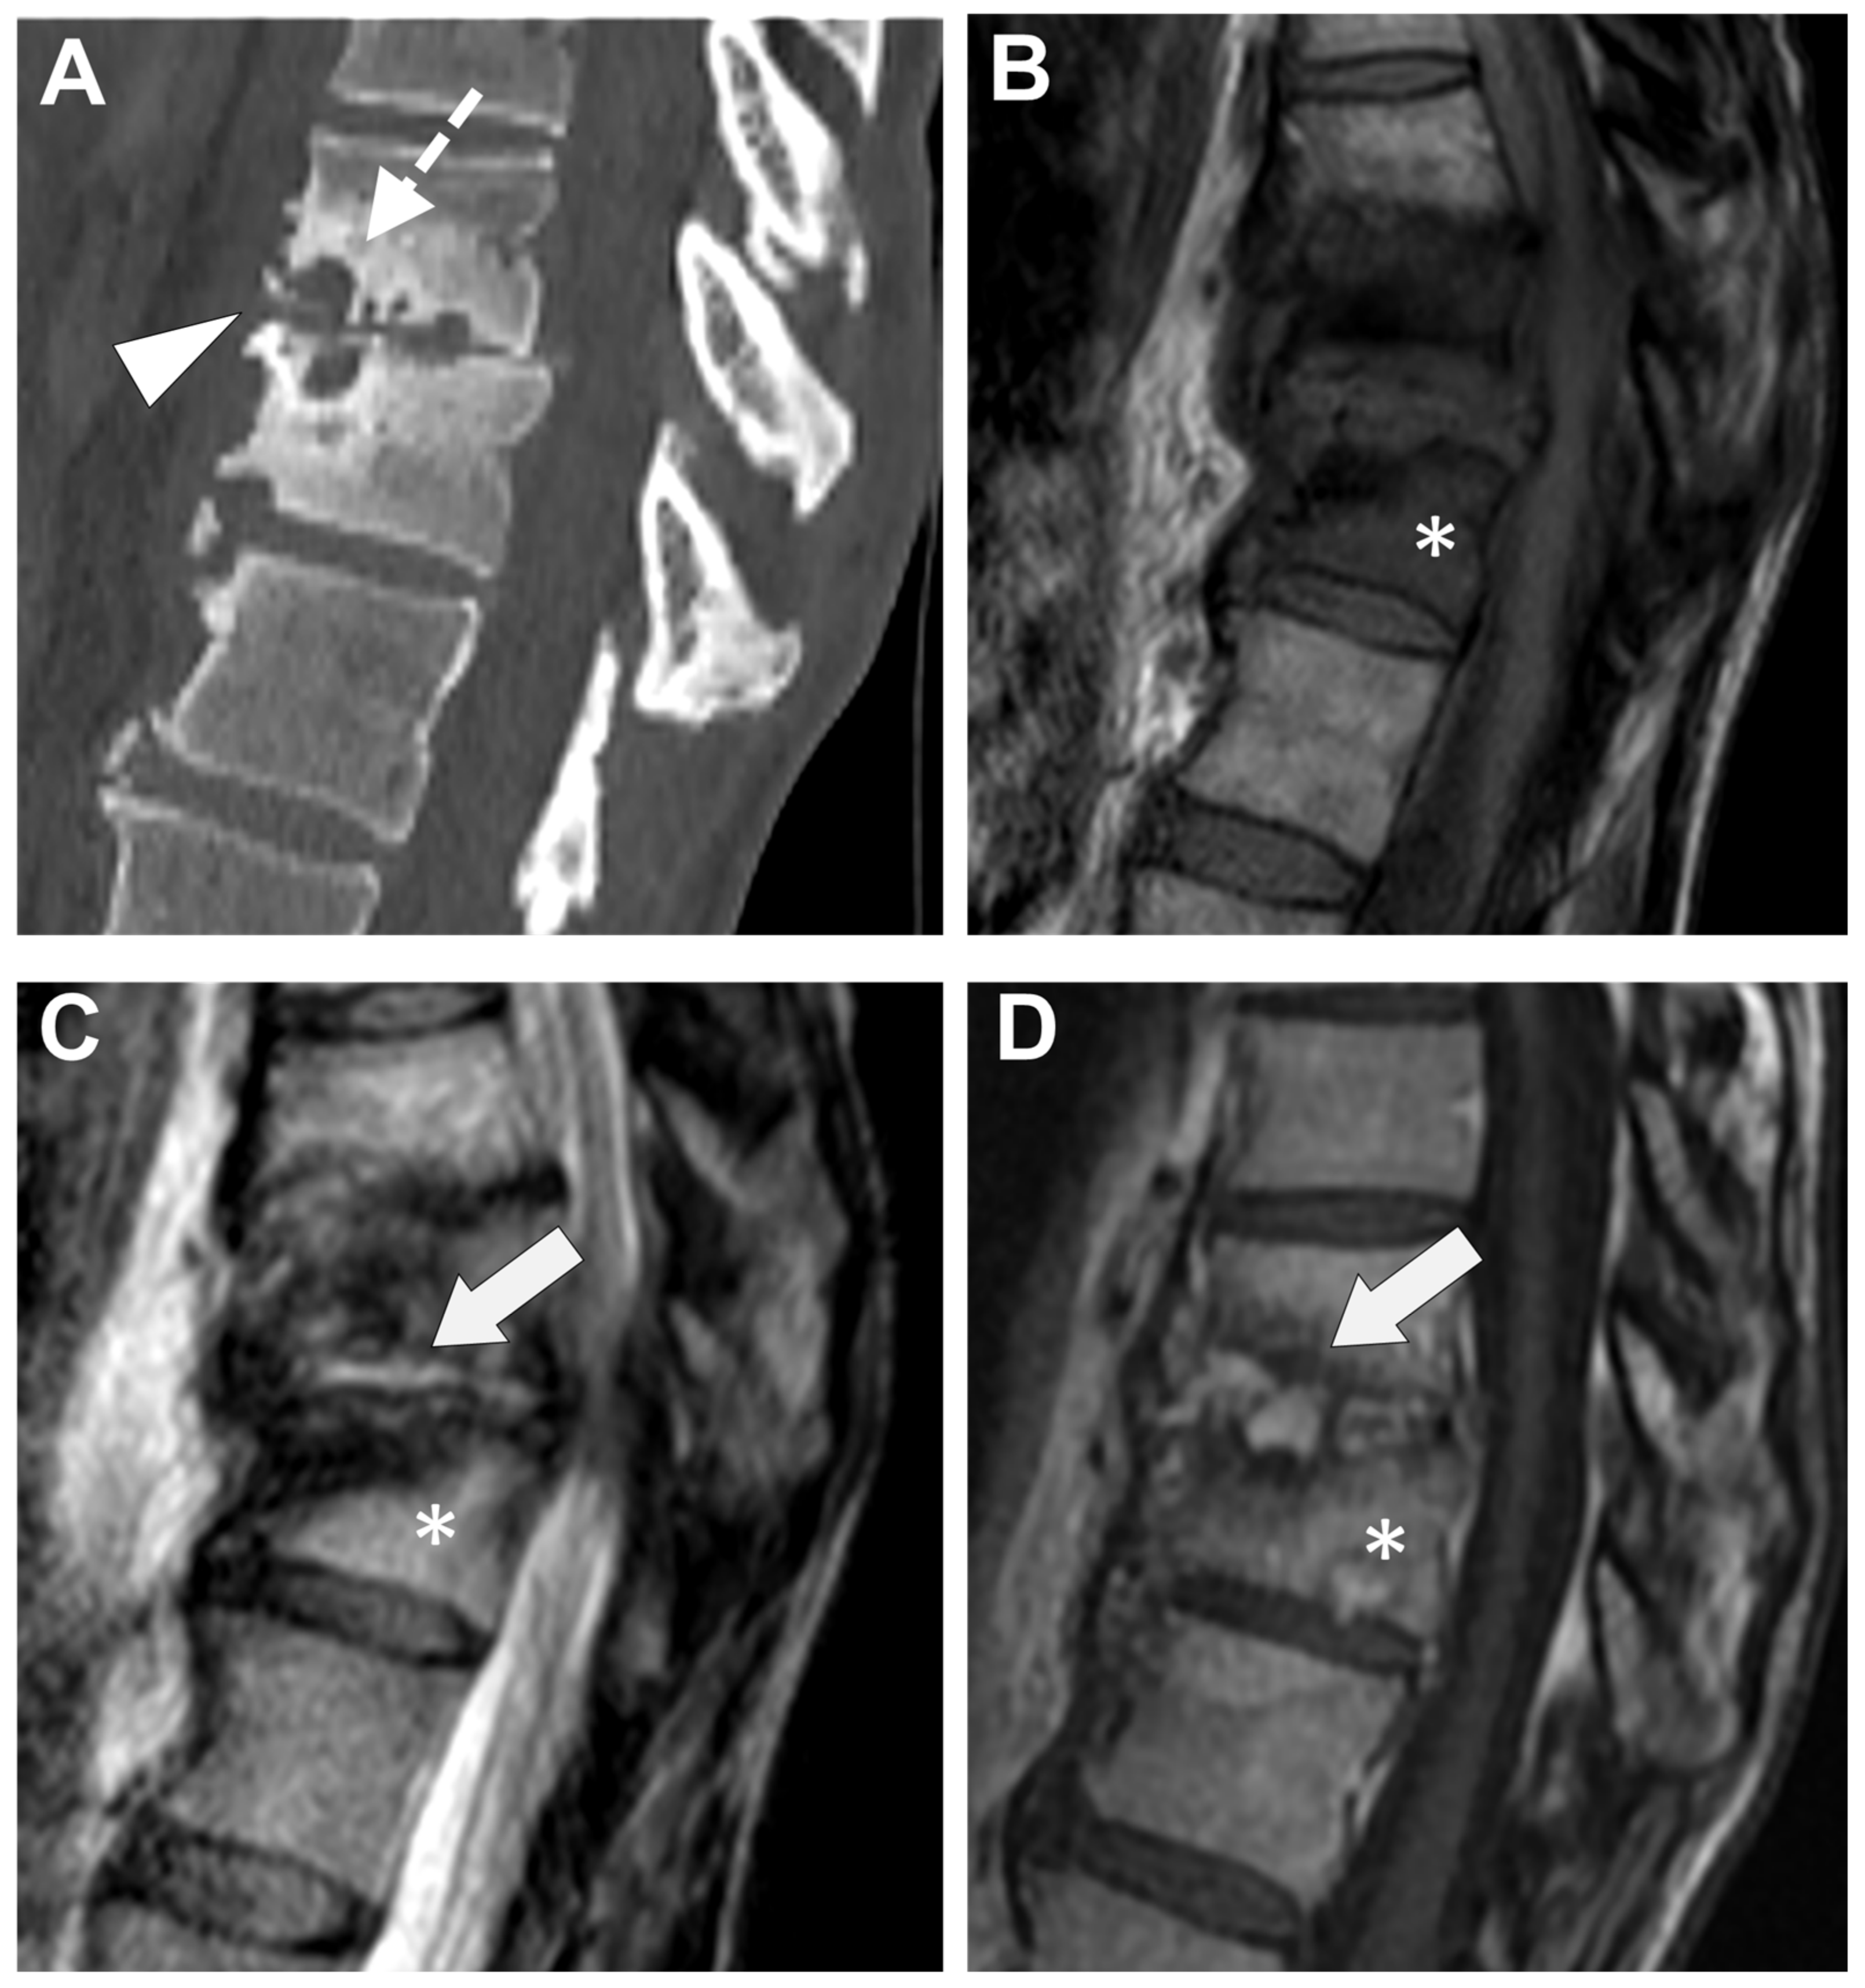

Figure 9. A 56-year-old male presented with a chronic and mechanic lumbar pain. An MRI was performed with (A) T1-weighted imaging (WI), (B) T2-WI, and (C) fat suppressed T2-WI. It demonstrates multiple Schmorl nodes (arrowheads) and a linear high signal intensity (SI) of the subchondral bones on both side of the L2-L3 level (arrows). There was no erosion, small anterior osteophyte, and degenerative disks. Hence, Modic 1 was diagnosed.

Degenerative end plate changes at the early inflammatory phase (Modic 1) can demonstrate some similar radiological features with infectious spondylodiscitis [72,73], that is to say, irregular end plate contours, possible subchondral cysts, and vertebral edema with a horizontal orientation (with high signal intensity on T2-WI—more pronounced with fat suppression method, low signal intensity on T1-WI, and, when performed, possible contrast-enhancement)—Figure 9.

However, additional features can rectify a misdiagnosis. First, the disk thinning is generally extended to the whole disk with low disk signal intensity on T2-WI. Second, on the T1-WI sequence and DIXON fat-saturated sequence, there is still a fatty signal intensity of the end plate. Third, the end plate borders are usually spared and remain continuous. Fourth, the surrounding soft tissues and epidural spaces should be spared. Third, associations with Modic 2 (i.e., healing process with fatty replacement of the vertebral endplate) and Modic 3 (i.e., healing process with sclerosis or hardening of the vertebral end plate) changes are frequent. It must be noted that erosions can happen during this inflammatory degeneration of the disk but without major destruction. Lastly, it has been suggested that DWI could help discriminate Modic 1 from infectious spondylodiscitis, but heterogeneous acquisition parameters have precluded from identifying ADC cut-off with sufficient diagnostic accuracy [74]. However, some qualitative DWI characteristics seem to remain relevant to diagnose Modic 1, such as the ‘claw sign’ [75]. It consists of a linear and paired area with high signal intensity on DWI and well-defined margins, whereas infectious spondylodiscitis would provide ill-defined diffuse (or unpaired) signal abnormalities on DWI [74,75].